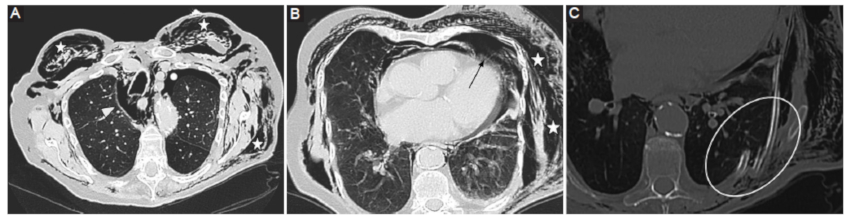

Neumopericardio

Entidad definida por la presencia de aire contenido entre ambas hojas del pericardio. Si bien puede darse de forma idiopática, las causas más frecuentes son postraumática y posquirúrgica (Figs. 3 y 4), secundaria a patología de órganos adyacentes (tubo digestivo o vía aérea) o afecciones del pericardio por gérmenes productores de gas9.

La gravedad del cuadro viene determinada por la posibilidad de desarrollarse un neumopericardio a tensión, el cual genera un síndrome de taponamiento cardiaco con descompensación hemodinámica y requiriendo descompresión de urgencia9.

La TCMC pone en evidencia la presencia de aire contenido entre las hojas del pericardio, aunque en situaciones de urgencia el diagnóstico de taponamiento cardiaco suele ser clínico6.